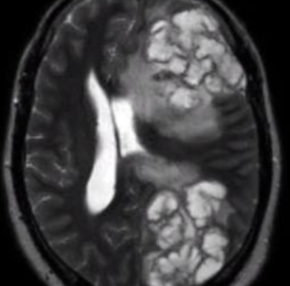

Diseminación a SNC - SIDA

Cuál es la manifestación clínica más frecuente de CRIPTOCOCCUS NEOFORMANS?

Criptocosis meníngea